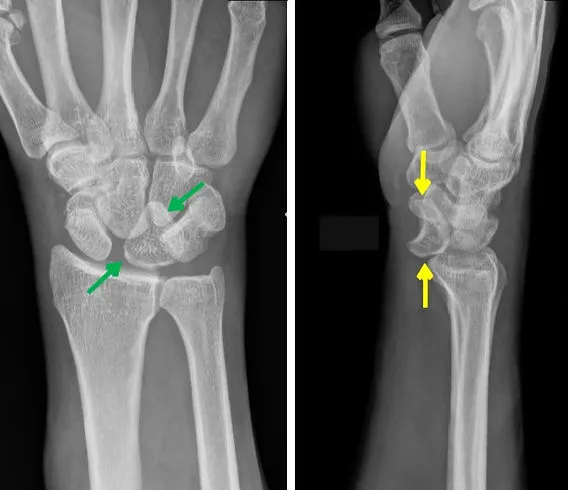

- Lunate/Perilunate Dislocation: High energy. FOOSH.

- Lunate dislocation: "Spilled teacup" sign (lateral X-ray).

- Perilunate: Other carpals dislocate dorsally.

- Scapholunate (SL) Dissociation: FOOSH. SL gap >3mm (Terry Thomas sign). Watson scaphoid shift test. Leads to SLAC wrist.